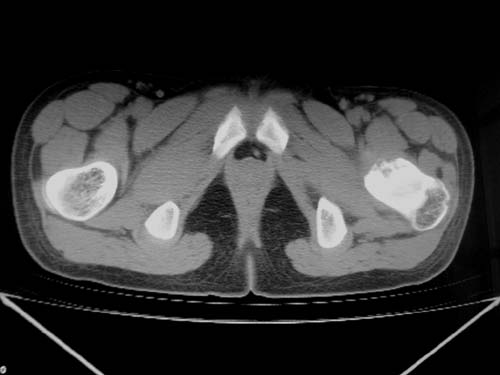

标题: CT19608:女12岁,左髋部疼痛,无发热病史 [打印本页]

标题: CT19608:女12岁,左髋部疼痛,无发热病史

左股骨干增粗,磨玻璃样改变——考虑骨纤维异常增殖症!

考虑左股骨上段骨纤维异常增殖症。

左股骨干增粗,磨玻璃样改变——考虑骨纤维异常增殖症!骨化性纤维瘤?